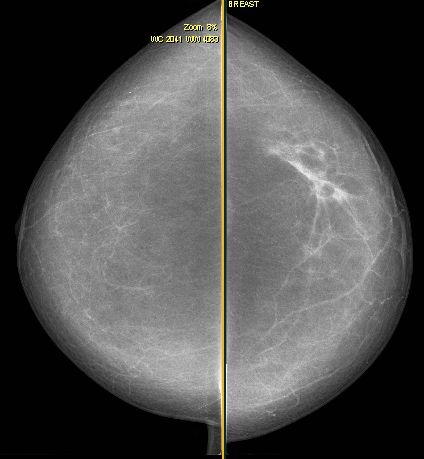

| Beispiele | invasives duktales Karzinom | klassische Trias: Kernschatten, strahlige Ausläufer, Mikrokalk![]() |